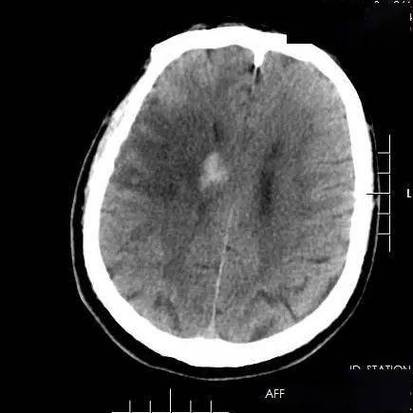

- 这次检查的“新发现”:这次您去做脑CT,可能是因为头晕、头痛、肢体麻木、无力或其他神经系统症状,医生在做这次检查时,意外地发现了您大脑里有一些陈旧性的病灶,这些病灶是之前发生过脑梗死的痕迹,就像皮肤上留下的旧疤痕一样。

- “陈旧性”是关键:这个词非常重要,说明这次的梗塞是过去发生的,而不是正在进行的急性期,如果您是刚刚发生脑梗,CT上可能不会立刻显示出典型的梗塞灶(通常需要24小时后才能清晰看到),而且您当时肯定会有非常典型的急性症状,如口角歪斜、肢体瘫痪、失语等,需要立即急诊。

- 您可能没有察觉:很多“陈旧性脑梗塞”是在发生时症状非常轻微,甚至完全没有症状(医学上称为“无症状性脑梗塞”或“静息性脑梗塞”),所以您自己可能都不知道曾经发生过,这种情况在老年人中尤其常见。